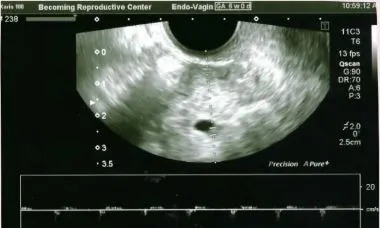

五週半時終於升到了1800,照了超音波似乎子宮內隱約有一個胎囊,不是很樂觀。

今天六週她再回診,超音波終於確認了這個小小胚囊顯示出規律而有力的心跳,大家真是喜出望外😃